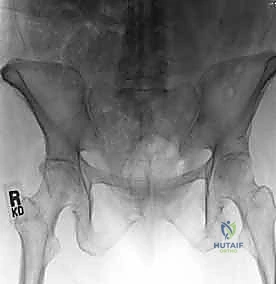

عند حدوث قوة قاهرة تفوق قدرة تحمل هذه الأربطة، يتمزق المفصل وتنفصل عظام العانة عن بعضها، وهو ما يُعرف طبياً بـ "كسر الكتاب المفتوح" (Open Book Fracture) إذا تجاوز الانفصال 2.5 سم. هذا الانفصال يؤدي إلى عدم استقرار كامل في الحلقة الحوضية.

يتم تقييم المريض بشكل شامل (أشعة سينية، أشعة مقطعية ثلاثية الأبعاد) لتحديد حجم الإصابة بدقة. تُجرى العملية تحت التخدير العام لضمان استرخاء العضلات بالكامل وعدم شعور المريض بأي ألم. يتم وضع المريض على ظهره على طاولة العمليات، وتُعقم منطقة البطن والحوض بالكامل.